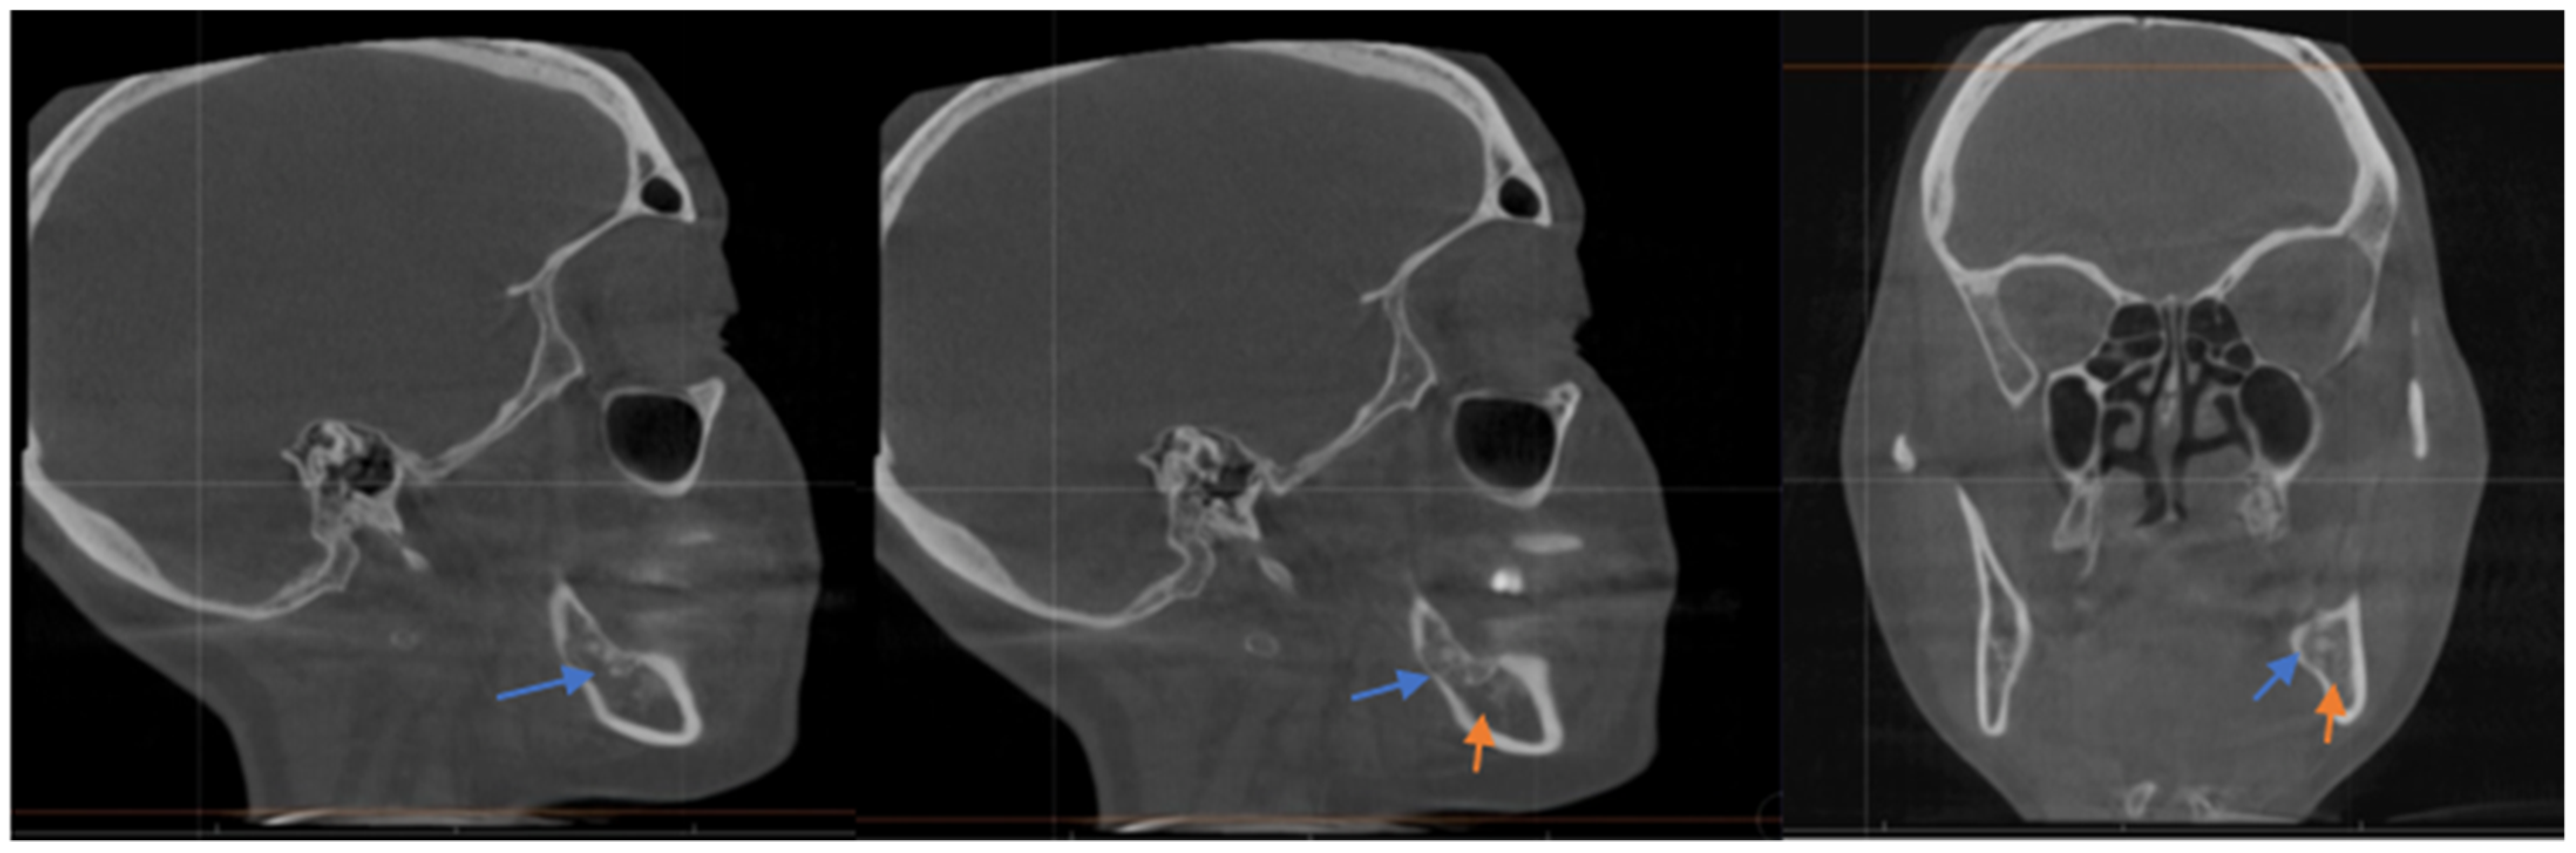

The injection site is identified initially by assessing the exact location of the mental foramen on a cone-beam computed tomography (CBCT) or panoramic radiograph. Most frequently, the foramen is situated between the apices of the first and second lower premolars or just below the apex of the lower second premolar.

The lower lip on the injection side is retracted gently and the foramen is then identified using a dental syringe and needle or directly with the tuberculin syringe and 30 gauge needle. Lidocaine 1% plain may be injected prior to the BTX-A, depending on the patient’s preference. The 0.4 cc of BTX-A is injected at a 45–60-degree angle to the mandible, and the needle is initially advanced 2–3 mm, at which point, it usually contacts the bone of the mandible. Once the foramen is located, the needle can be further advanced an additional 2 mm just beyond the opening of the mental foramen. The BTX-A is then injected slowly to avoid pain or potential nerve injury (see Figure 1). Even without prior local anesthetic, the patient will report paresthesia for a couple of hours, which is frequently welcomed by the patient.

Figure 1. The technique demonstrated is used to locate the mental foramen and deposit a small amount of local anesthetic followed by Botulinum toxin type A as a treatment for trigeminal neuralgia.